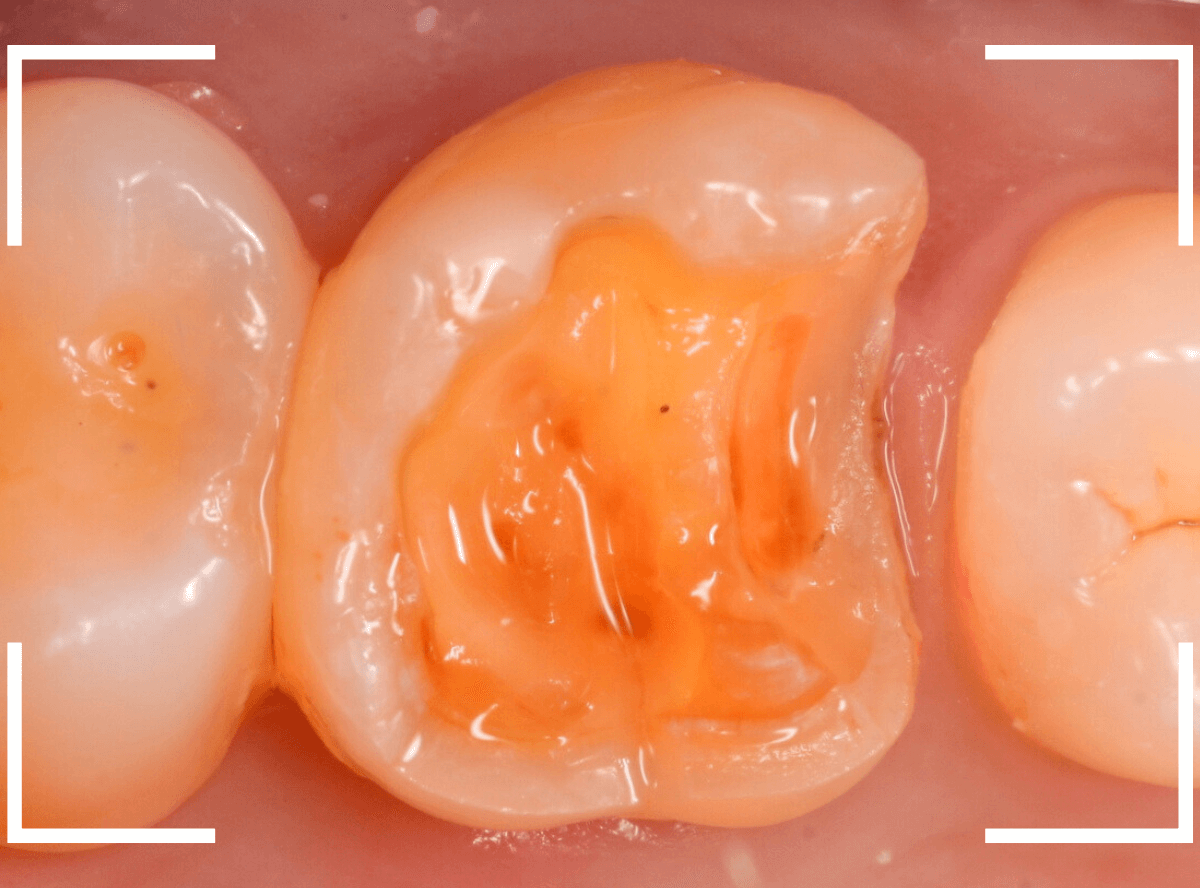

虫歯の治療を開始します。

隣の歯とのすき間を中心に広い虫歯になっていました。

虫歯治療後、特に症状もなく経過観察できましたので、つめものを作る治療に入ります。

セラミック治療をご希望されましたので、

小臼歯をE-MAX・インレー、

大臼歯をジルコニア・インレーで処置することになりました。